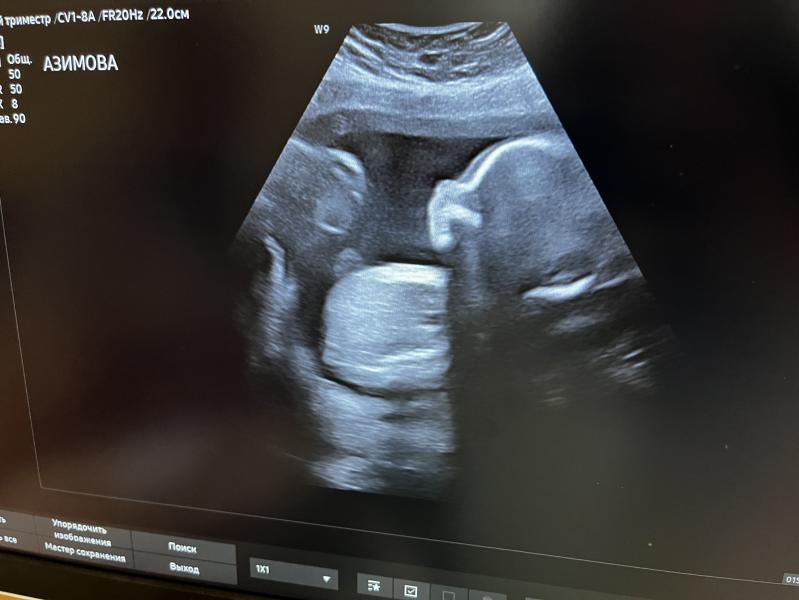

2 скрининг: все хорошо! Малыш 423 грамма, шейка 37 мм, плацента 45 мм от края – ждем сыночка!

2 скрининг пройден)) вчера была) 423 грамма уже мой богатырь) все показатели - идеальны , шейка 37, плацента от края -45 🥰 ждем тебя, сынок